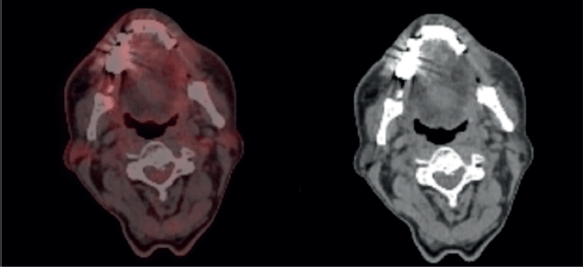

To assess the extent of the condition, an 18F-fluorodeoxyglucose positron emission tomography (PET)/CT scan was performed, revealing an Fluorodeoxyglucose (FDG)-avid left lower lip lesion measuring 4.5 × 1.5 × 2.8 cm with a maximum standardised uptake value (max) of 15.66 (Figure 2). A repeat biopsy and IHC profiling of the left lower lip lesion demonstrated positivity for CD3 and CD56, a loss of CD5 staining in CD3-positive cells, a reserved CD4/CD8 ratio and negativity for CD20, TdT and EBV status. Additionally, a Ki-67 proliferative index of approximately 50% further supported the diagnosis of P-TCL NOS (Figure 3).

Figure 2. Pre-chemotherapy PET CT scan, showing FDG avid lesion involving left lower lip.